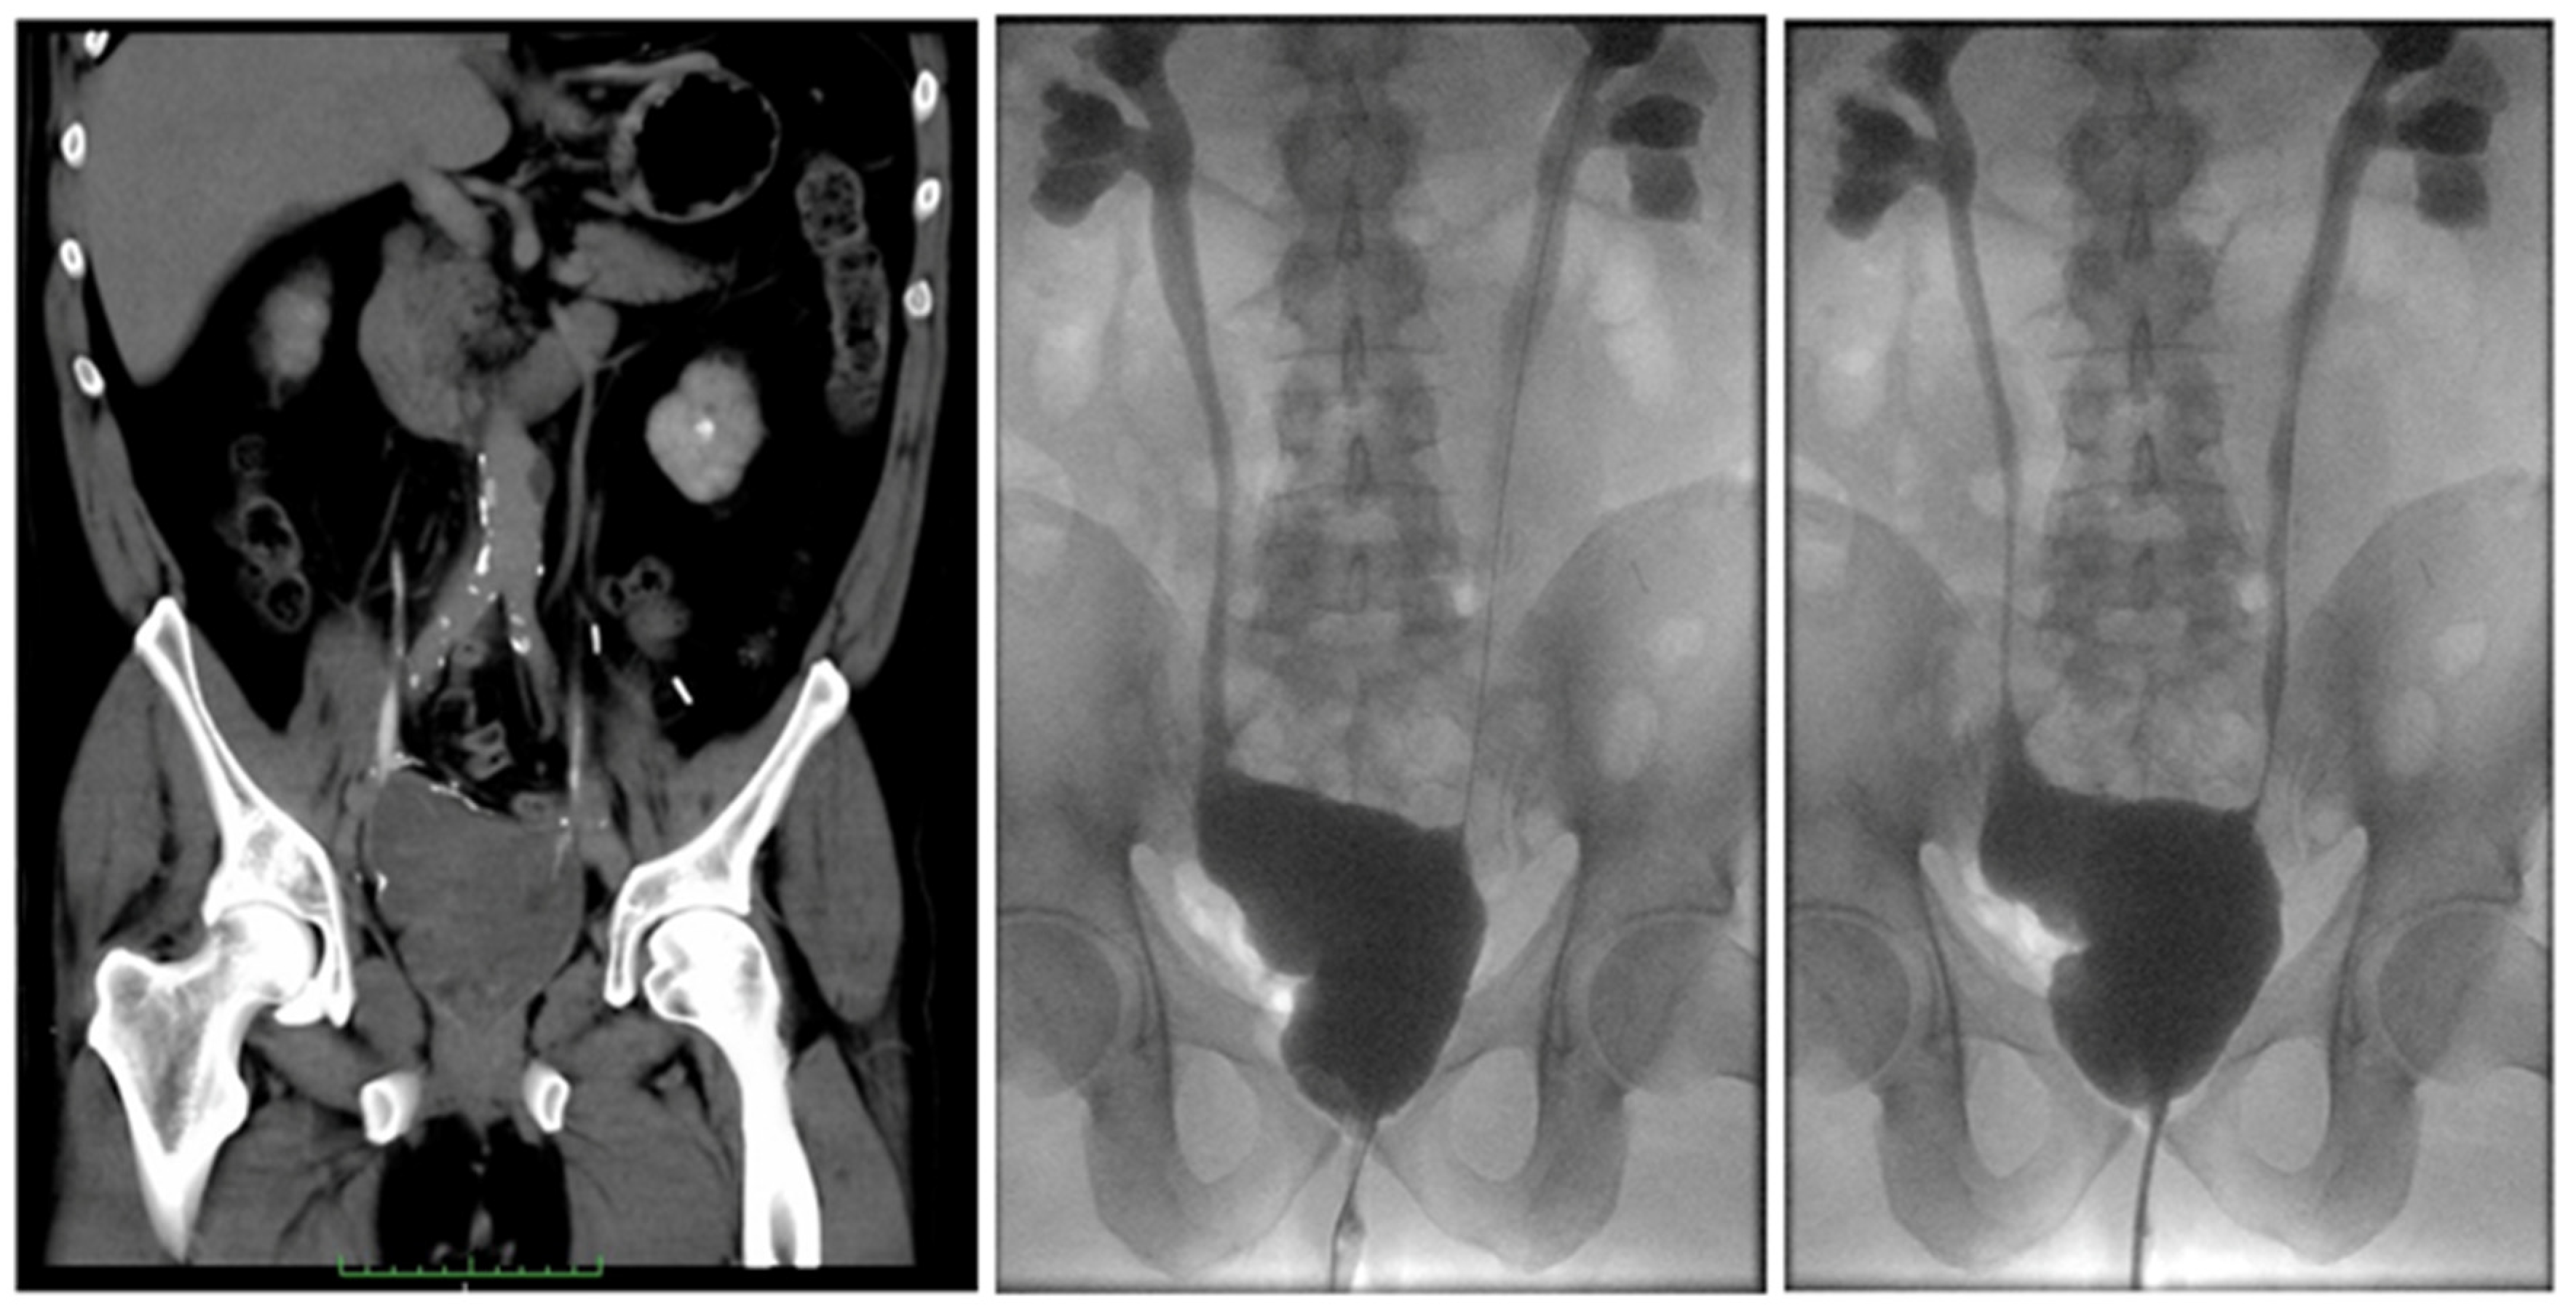

Successful Multidisciplinary Repair of Severe Bilateral Uretero-Enteric Stricture with Inflammatory Reaction Extending to the Left Iliac Artery, after Robotic Radical Cystectomy and Intracorporeal Ileal Neobladder

2. Case Report